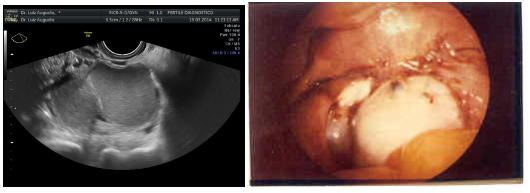

A ultrassonografia é utilizada predominantemente na avaliação dos ovários e investigação da pelve na dor pélvica e infertilidade. Sendo o método inicial de escolha para a identificação e caracterização de componentes císticos anexiais.

A sensibilidade no diagnóstico de endometriomas com o USG-TV é alta, chegando entre 92-97%, sendo a especificidade de 98%. A acurácia do diagnóstico pode ser aumentada com a avaliação por Doppler, em que o fluxo sanguíneo nos endometriomas é frequentemente pericístico com um índice de resistência por volta de 0,45.